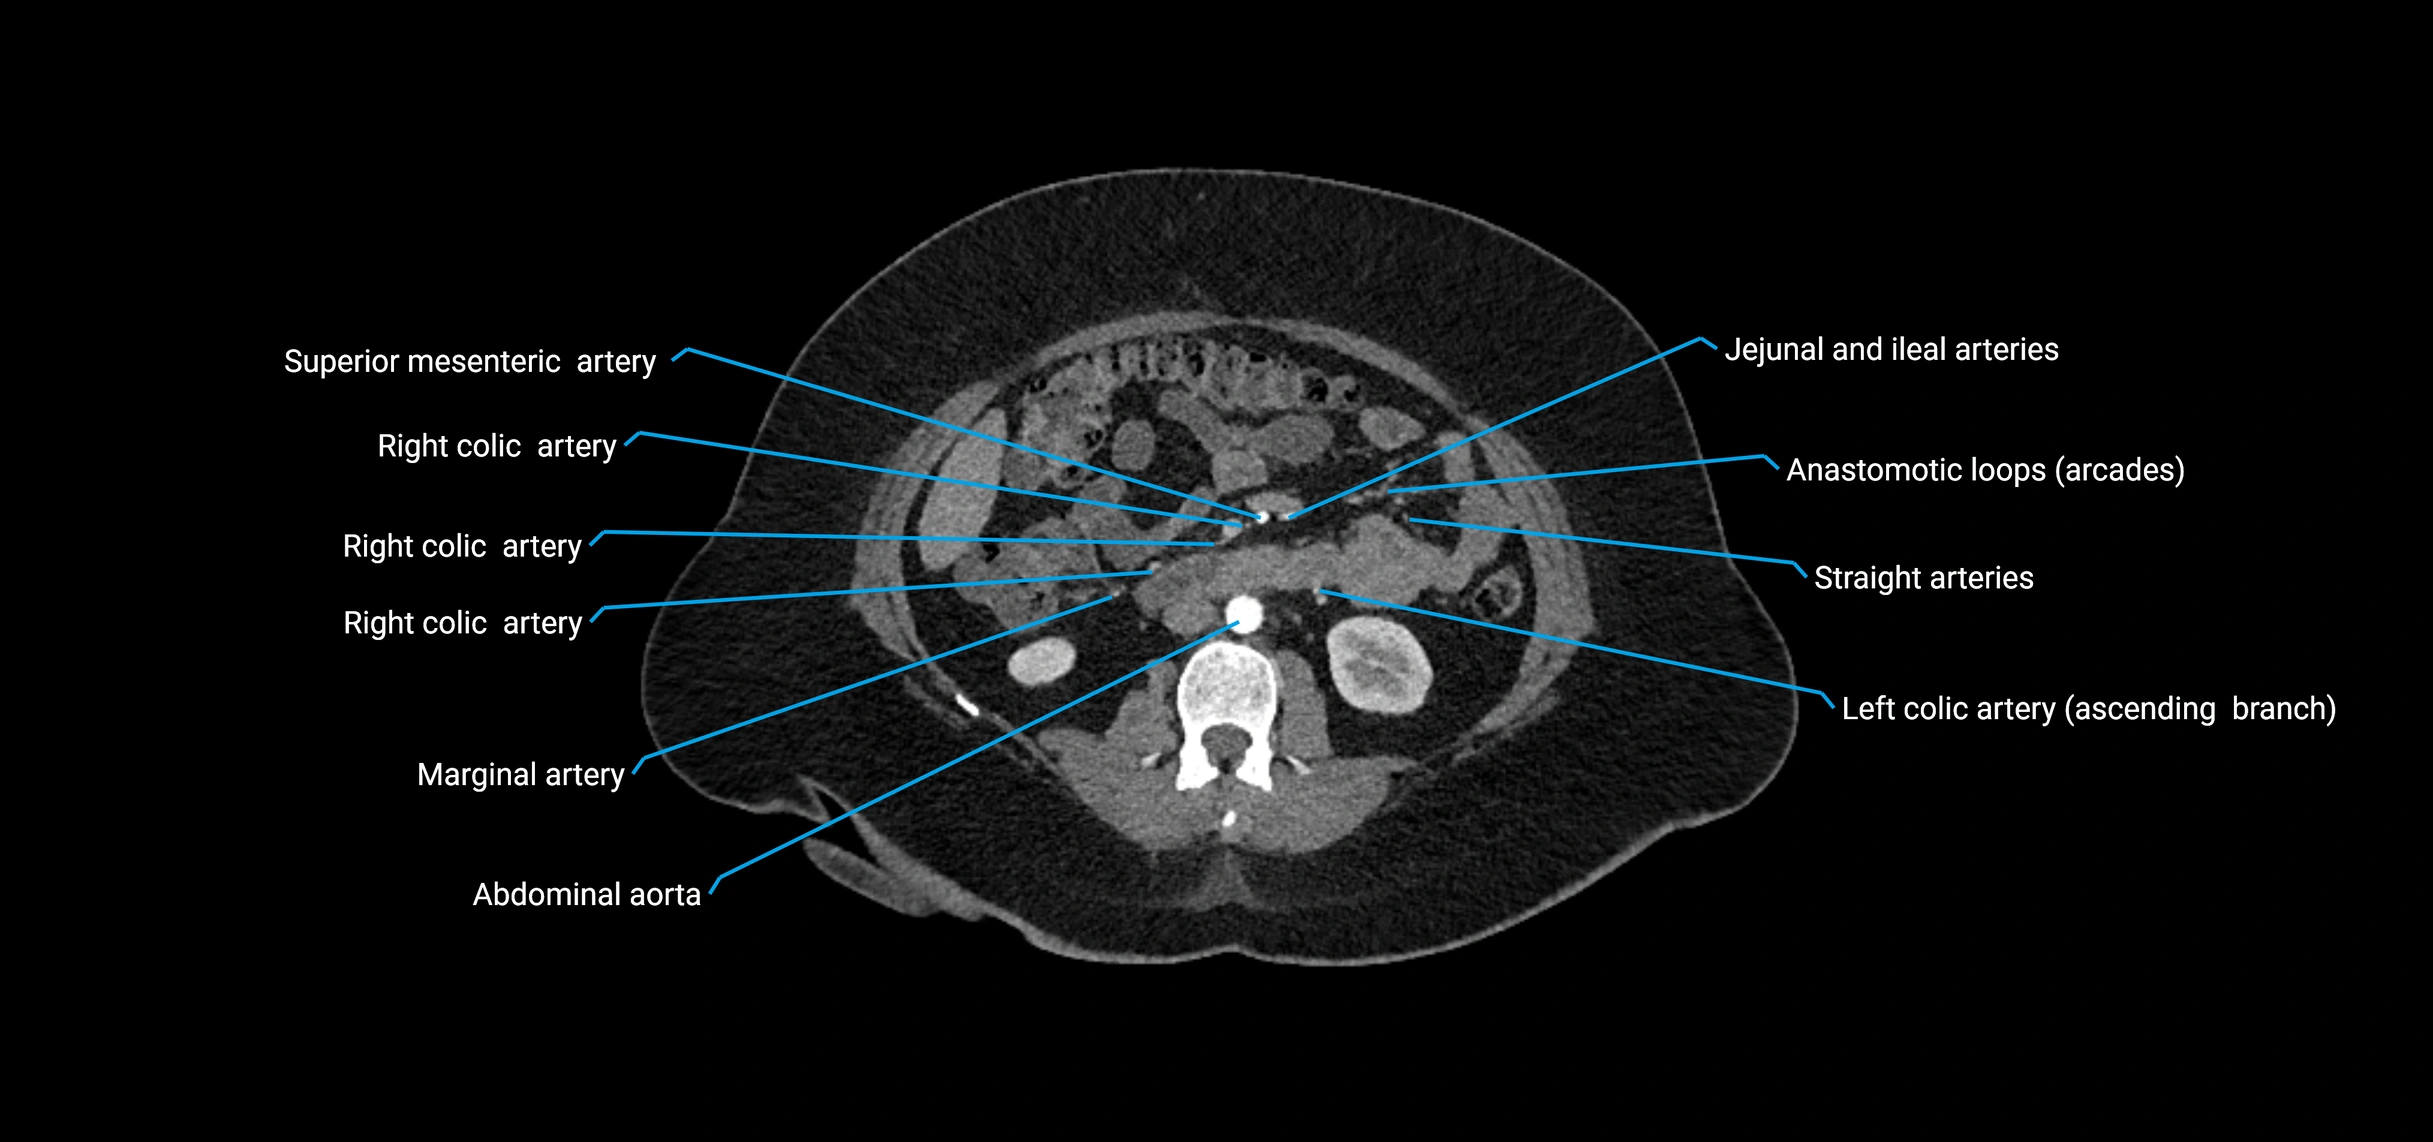

Contrast-enhanced CT (CTA):

• Gold standard for abdominal aortic imaging

• Provides excellent detail of lumen, wall, aneurysm, thrombus, and branch vessels

• Multiplanar and 3D reconstructions help in aneurysm measurement, stent graft planning, and dissection evaluation

• Detects acute rupture, traumatic injury, or occlusion with high sensitivity